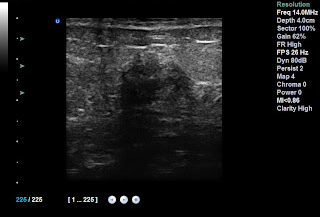

Ecografía

Ventajas: Excelente en detección de

lesiones benignas, buena en lesiones malignas de 1 cm o más, No emite radiación,

Suele ser confortable para la paciente (exceptuando el gel frío), diagnostica

con mucha facilidad en mamas densas (es excepcional en lesiones quísticas).

Desventajas: Es operador dependiente (es

decir, la experiencia del operador es fundamental para un diagnóstico y exploración

apropiada), con frecuencia quedan segmento de mama sin explorar, no detecta

microcalcificaciones, la sensibilidad de la ecografía es similar a la mamografía,

pero es más alta en mamas densas, sin embargo, también tiene un valor más

alto de falsos positivos (lesiones que parecen sospechosas para cáncer, pero

que a la biopsia resultan benignas).